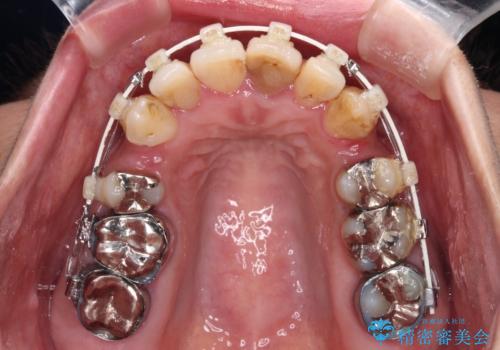

- 矯正装置

- 審美装置

- 歯列全体が内側に倒れ込んでいることと、口元の突出感を気にして来院された患者様です。

上下ともに歯列が狭窄しており、前方に突出している状態でした。

歯が重なるような叢生も認められたため、上下左右の第一小臼歯4本を抜歯して、口元が引っ込むように治療を行うこととしました。

口元を引っ込めることができたため、口を閉じるときに力が入っていて皺のよっていた顎先も、スムーズに閉じられるようになったことで力がかからなくなりました。